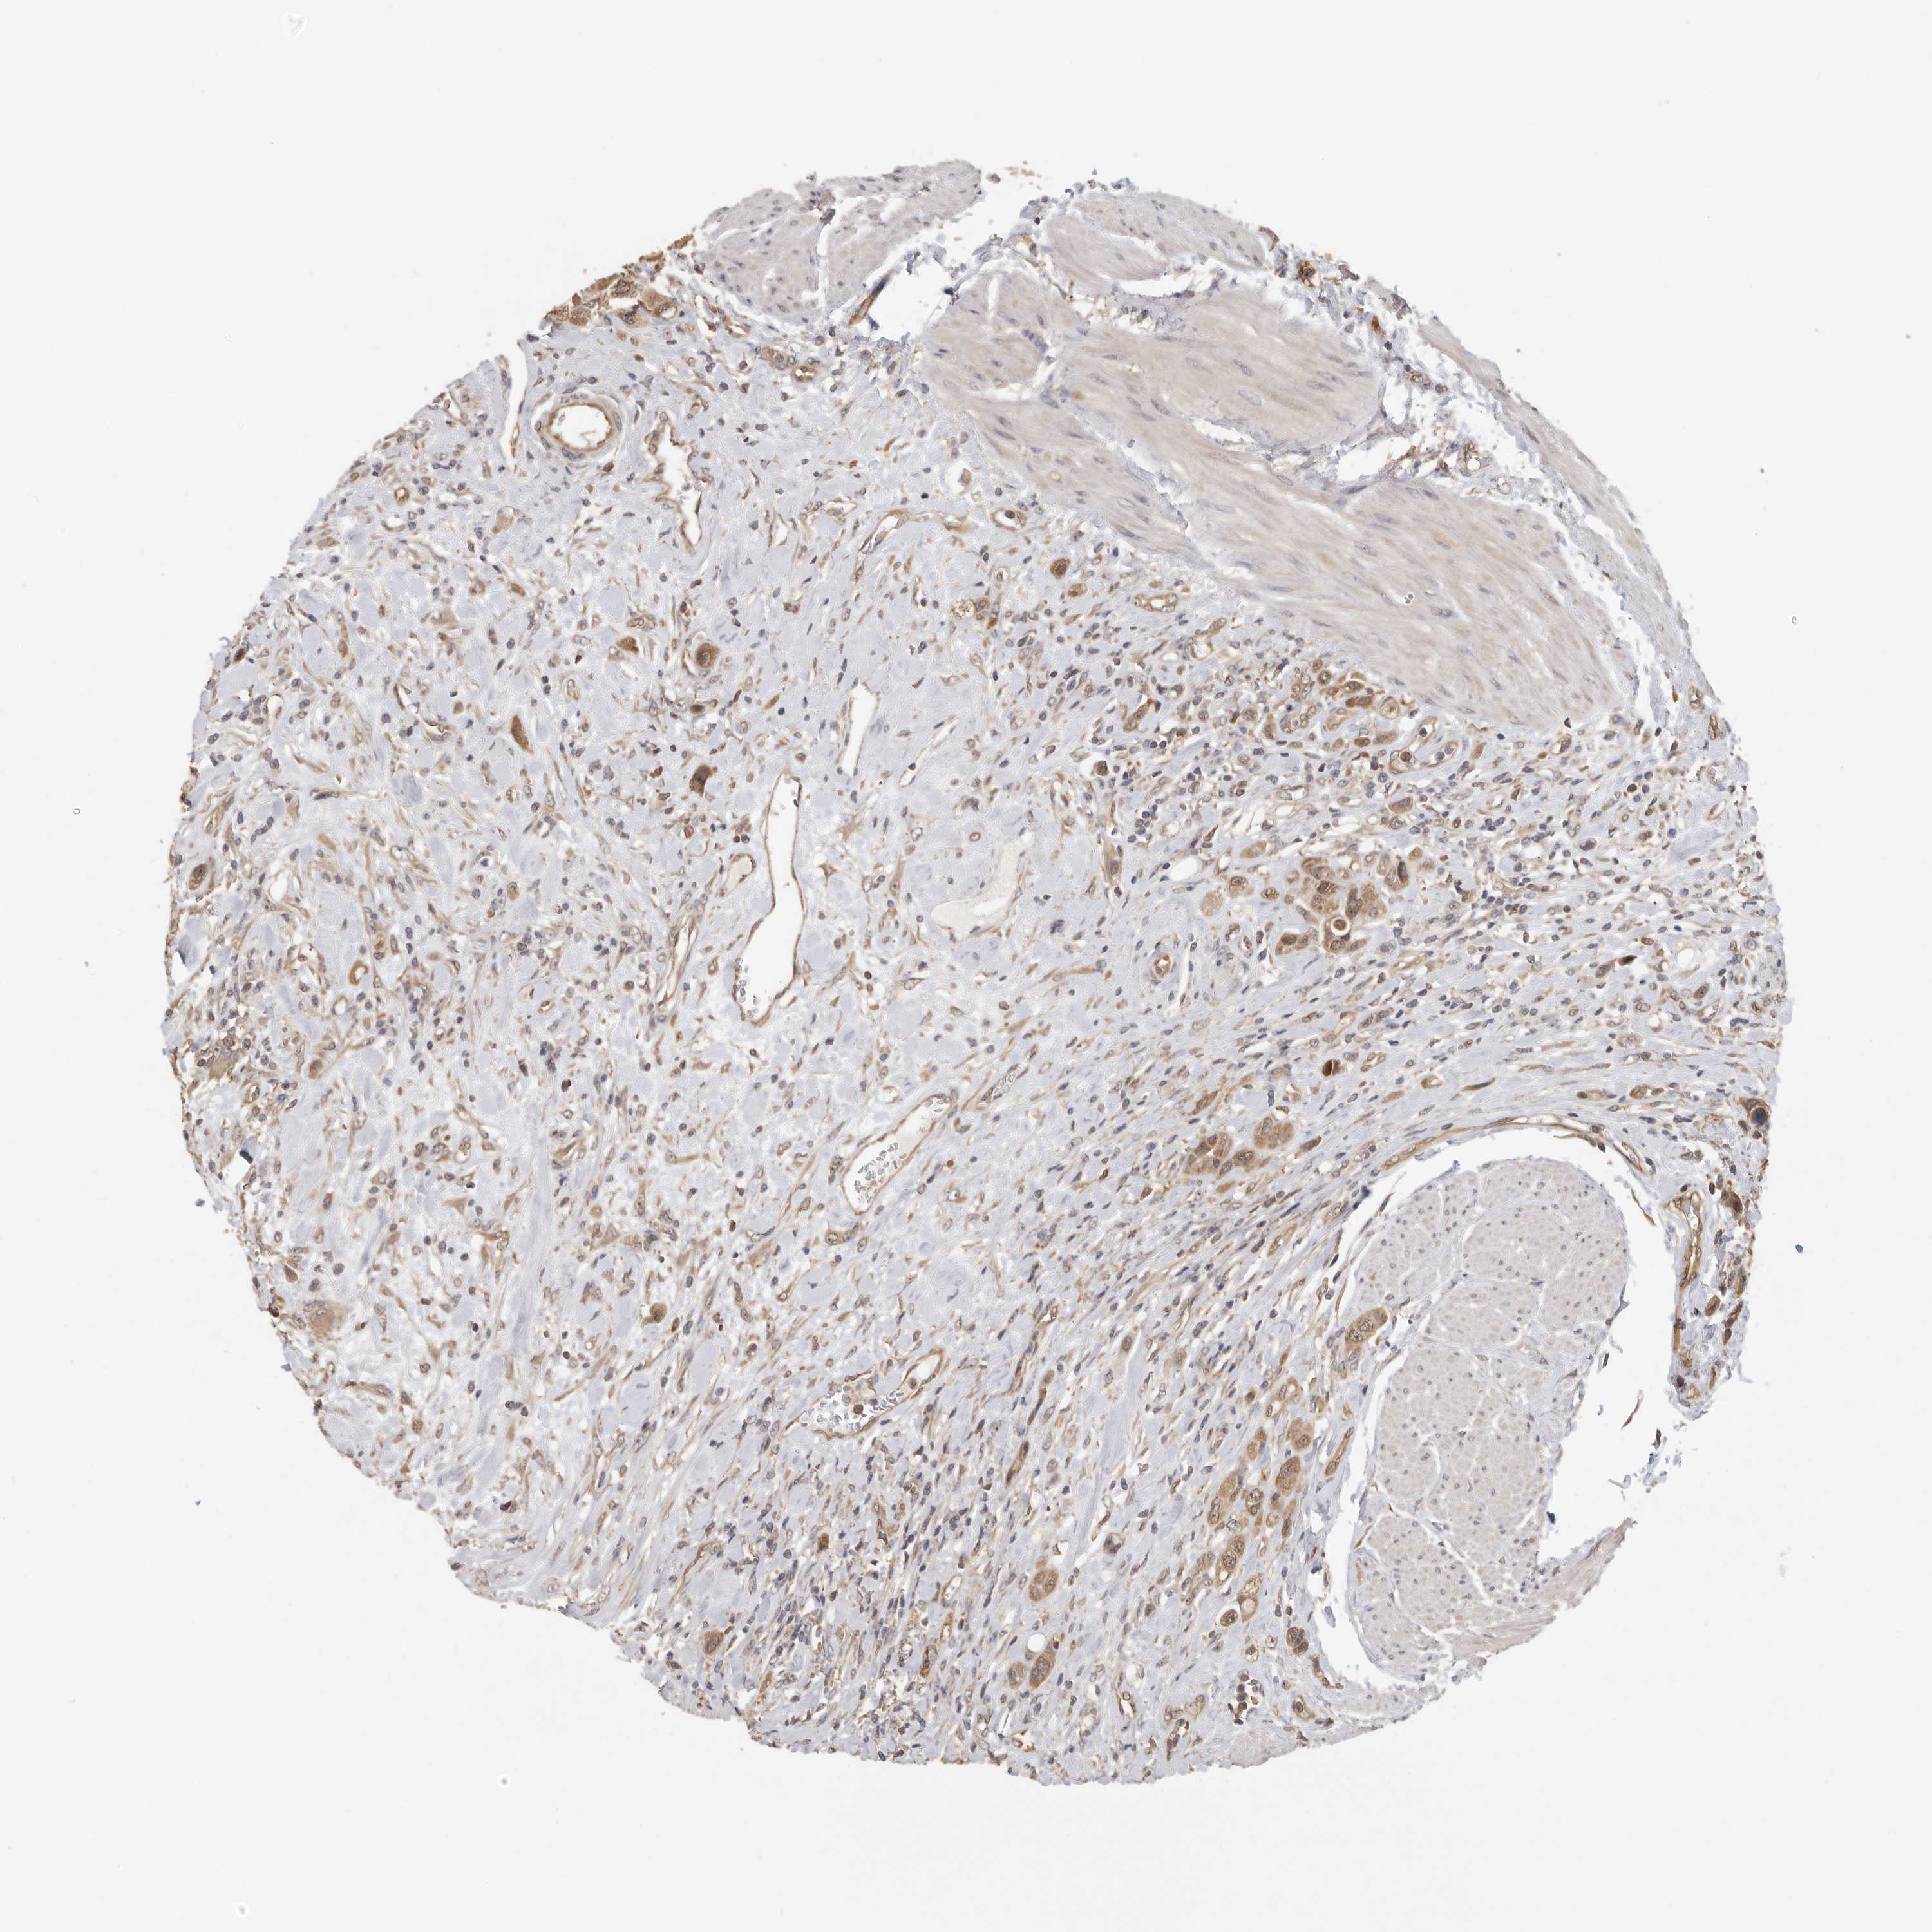

UROTHELIAL CANCER - Protein expressioni

A mouse-over function shows sample information and annotation data. Click on an image to view it in a full screen mode. Samples can be filtered based on level of antibody staining by selecting one or several of the following categories: high, medium, low and not detected. The assay and annotation is described here.

Note that samples used for immunohistochemistry by the Human Protein Atlas do not correspond to samples in the TCGA dataset.

Antibody stainingi

Antibody staining in the annotated cell types in the current human tissue is reported as not detected, low, medium, or high, based on conventional immunohistochemistry profiling in selected tissues. This score is based on the combination of the staining intensity and fraction of stained cells.

Each image is clickable and will lead to virtual microscopy that enables deeper exploration of all samples and also displays staining intensity scores, fraction scores and subcellular localization as well as patient and tissue information for each sample.

Antibody HPA018520

Antibody HPA021051

Antibody HPA029426

Urothelial carcinoma, Low grade

Urothelial carcinoma, High grade